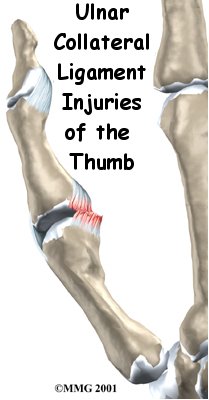

Ulnar Collateral Ligament Injuries of the Thumb

Injury to the ulnar collateral ligament of the thumb is fairly common. This strong band of tissue is attached to the middle joint of the thumb, the joint next to the web space of the thumb. This condition is sometimes called gamekeeper's thumb because Scottish gamekeepers commonly injured their thumbs as a result of their job.